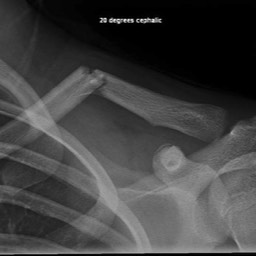

What do Distal Clavicle Fractures Look Like on X-ray and CT?

X-RAY

Click an image to enlarge